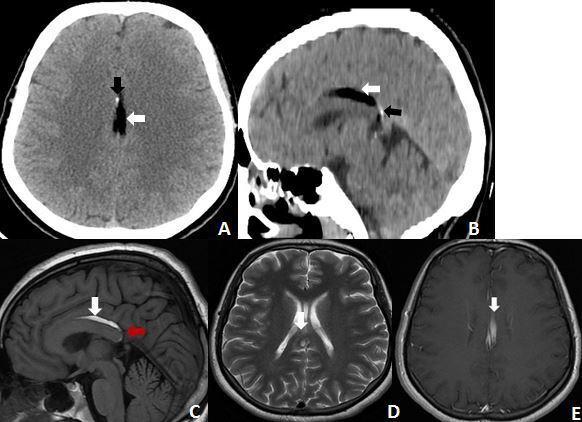

P lipomas are the most habitual location for an intracranial lipoma. They are fat-containing lesions arising from the interhemispheric fissure intimately related to the corpus callosum, which is often abnormal. They originate from aberrant differentiation of the persistent primitive meninx. Most Pericallosal lipomas are asymptomatic and come into clinical attention during neuroradiological investigations for other conditions. MRI is the modality of choice to characterize not only the extent of the lipoma but also the frequently associated agenesis/dysgenesis of the corpus callosum. Pericallosal lipomas can be divided into two groups: The Tubulonodular type and The curvilinear type. Curvilinear lipomas are less common than Tubulonodular. We report the clinical and radiological findings of curvilinear Pericallosal lipoma in two patients with corpus callosum abnormalities revealed incidentally during evaluation following trauma.

胼胝体脂肪瘤是颅内脂肪瘤最常见的部位。它们是起源于大脑半球间裂、与胼胝体密切相关的含脂肪病变,胼胝体常存在异常。它们起源于残留原始脑膜的异常分化。大多数胼胝体脂肪瘤无症状,在因其他疾病进行神经影像学检查时才引起临床关注。MRI不仅是确定脂肪瘤范围的首选检查方法,也是发现胼胝体常伴发的发育不全/发育异常的首选方法。胼胝体脂肪瘤可分为两组:管状结节型和曲线型。曲线型脂肪瘤比管状结节型少见。我们报告了两例在创伤后评估中偶然发现胼胝体异常的曲线型胼胝体脂肪瘤患者的临床和影像学表现。